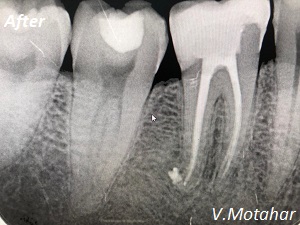

Root Canal Treatment on a molar tooth!

before

after